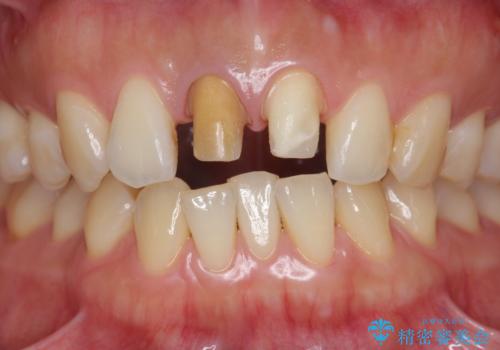

前歯の変色 根管治療と高品質セラミック歯科治療

- 前歯の変色の改善を求めて来院されました。

X線検査を行ったところ、共に深い虫歯が原因となり神経が死んでしまっている状態であることがわかり、根管治療を行ったのちセラミック補綴を行っていくこととなりました。